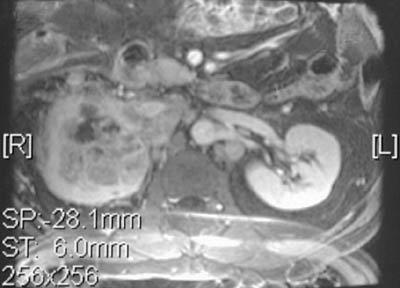

The axial MRI scans shown here reveal a renal cell carcinoma of the left kidney, seen with T1 weighting above and T2 weighting below.